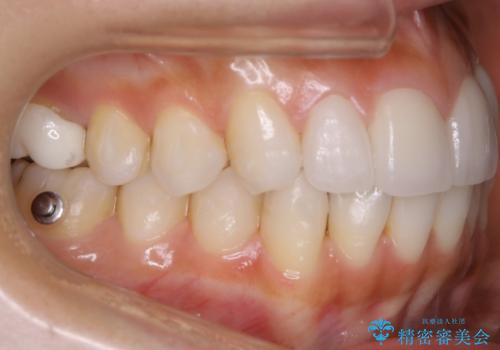

【非抜歯】噛み合わせを整えたい! インビザライン矯正

- 嚙み合わせのズレを主訴にご来院されました。

前歯・奥歯ともにセラミッククラウンで治療されている歯があったため、その歯にあまり影響が出ない範囲内で全体の噛み合わせが良くなるような動きを組み込んで治療を進めることとなりました。

矯正治療前にセラミック等の被せ物をされている場合、それ自体の外形は矯正治療では変更することができないため、その他の天然歯の移動に影響を与えてしまう場合があります。また、治療上設定されるアタッチメント(歯の表面に付けるプラスチックの突起)が付かない場合が多く、歯のコントロールが不足する場合があります。